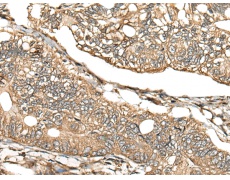

IHC positive control: |

Human gastric cancer |